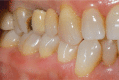

Figure 1

Lateral view of the initial clinical situation. Tooth N. 16 showed a substantial loss of structure resulting from caries; tooth N. 15 needed to be extracted due to a periodontal lesion.